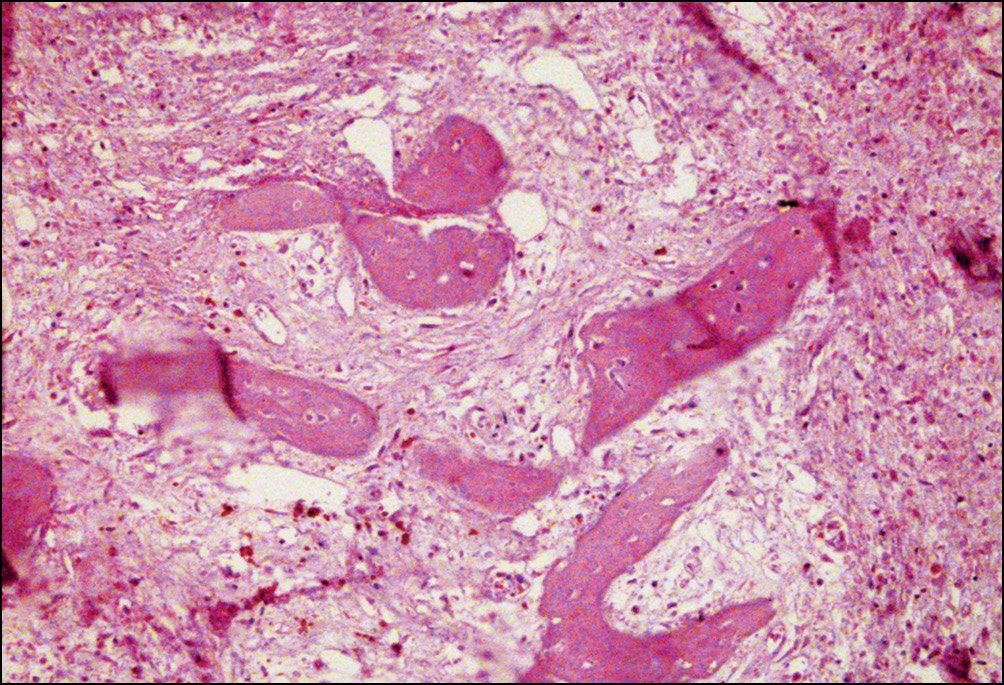

Местами репаративные процессы проявлялись разрастаниями волокнистой фиброзной ткани вокруг осколков костных балок, по-видимому, для последующего использования их как арматурный материал в костеобразовании (рис. 4).

Рис. 4. Репаративные изменения костной ткани в зоне перипротезных переломов бедренного компонента: разрастания волокнистой фиброзной ткани вокруг осколков костных балок. Окраска гематоксилином и эозином. Увел. ×160

Fig. 4. Reparative changes in periprosthetic fractures bone tissue of the femoral component: proliferation of fibrous tissue around the fragments of the bone beams. Staining with hematoxylin and eosin. Magnification × 160